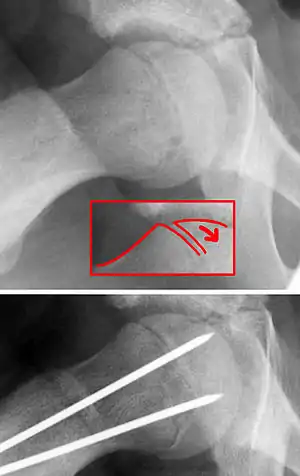

| X-ray showing a slipped capital femoral epiphysis, before and after surgical fixation. | |